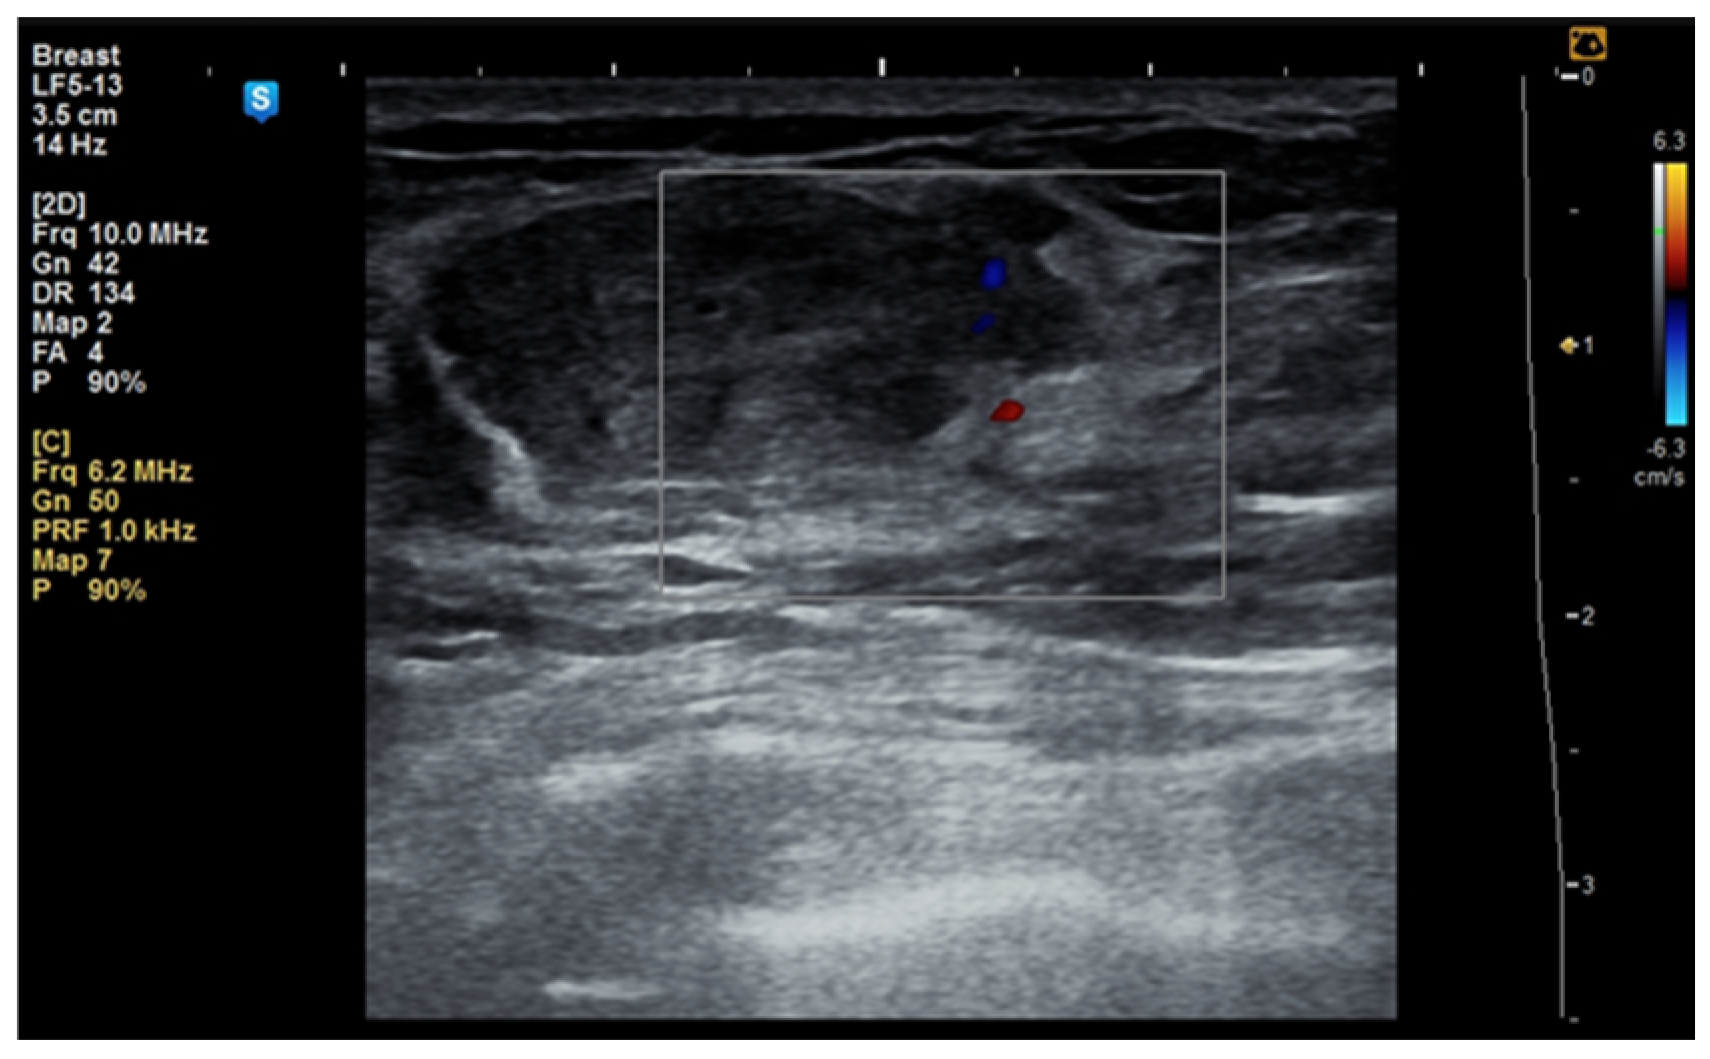

Although the literature identifies mammography as the primary diagnostic method for breast hamartomas, in our study, the diagnosis was established via ultrasound examination. This preference is due to the younger age of many patients, with only three being over 50 years old. On ultrasound, hamartomas typically appear as oval, well-circumscribed masses with heterogeneous hypoechoic or isoechoic echostructures and reduced or absent vascularity (Figure 1 and Figure 2). In our study, the concordance between ultrasound and histological size was 84.61%. Preoperative ultrasound diagnosis of hamartoma was established in only five patients, representing 38.46% of the cases.

Figure 2. Ultrasound image of a 53-year-old woman with a right breast hamartoma with reduced vascularity, located in the lower inner quadrant.